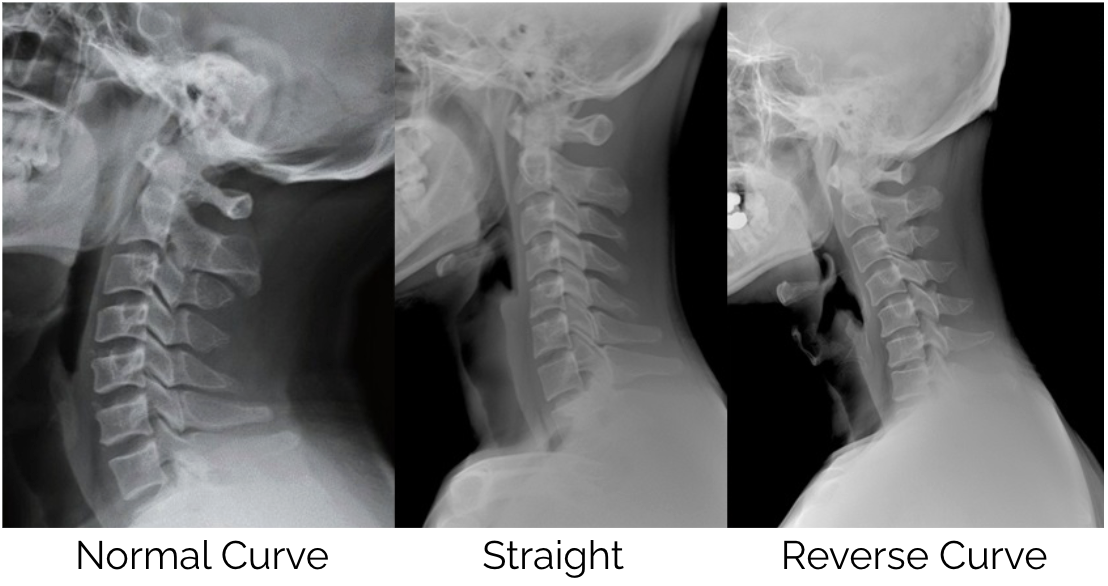

The consequences of sustained forward head posture extend well beyond local neck pain and muscle tension. Dr Hansraj’s research (1) also noted that spending several hours per day in poor posture can begin to alter the natural curvature of the cervical spine over time. A change that is far more difficult to address once it becomes established.

As chiropractors, we have seen a shift over the past 10-20 years, with more people losing the natural curve of the cervical spine and an increase in reversed curves which is a result of excessive time looking at handheld devices.